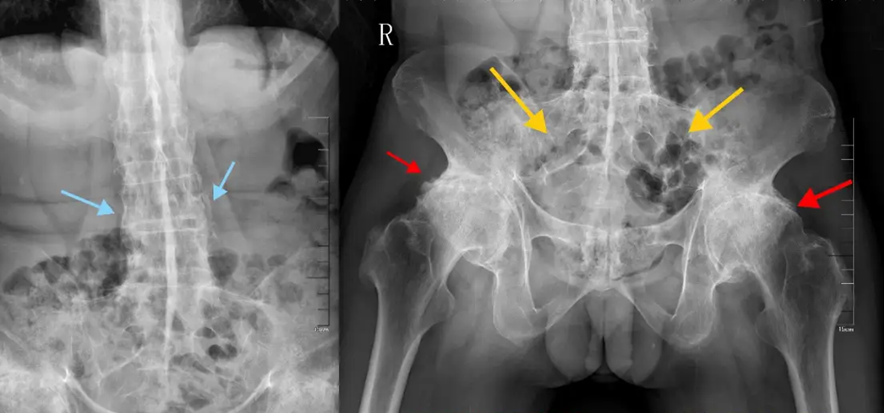

“Bệnh thường tấn công các khớp ở cột sống, khớp cùng - chậu, và hông. Khi tiến triển nặng, cột sống có thể dính cứng như một cây tre, khiến người bệnh không thể cúi, ngửa hay xoay lưng”, bác sĩ Vạn cho biết.

Bệnh tật 20 năm của Châu Kiệt Luân đang tấn công giới trẻ!- Ảnh 2.

Cột sống của bệnh nhân bị viêm cột sống dính khớp có những thay đổi "giống như cây tre"